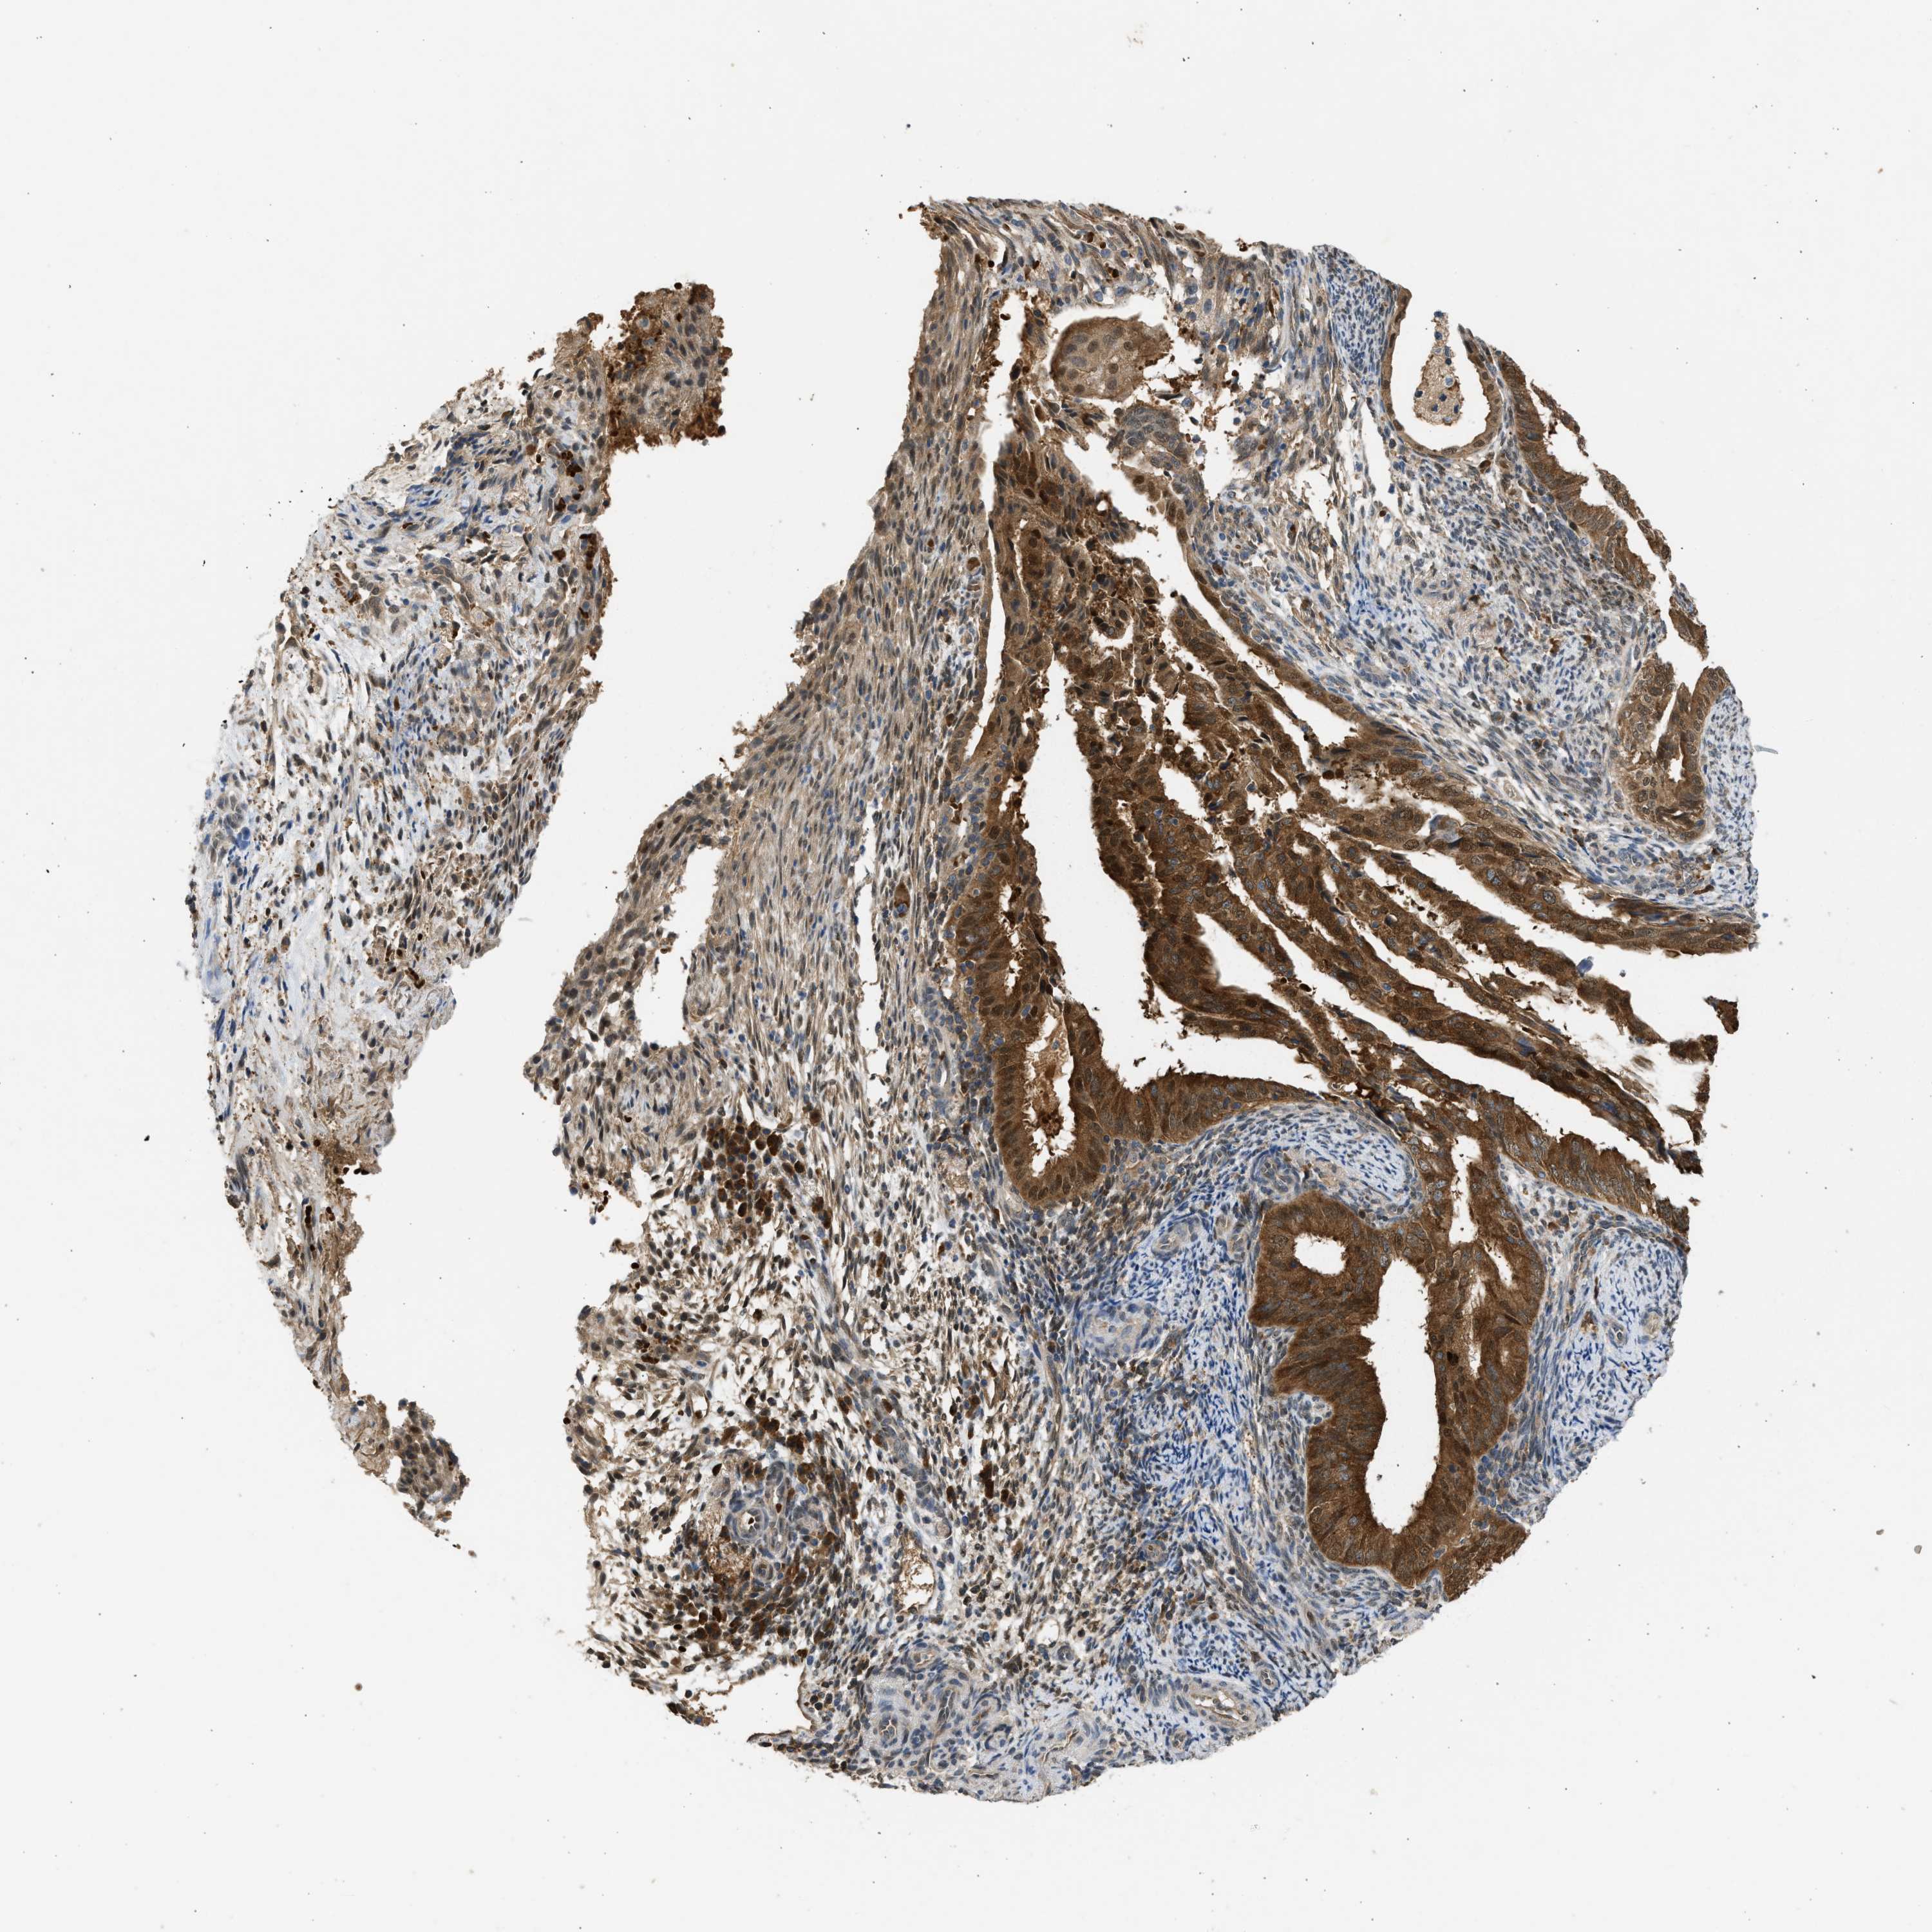

ENDOMETRIAL CANCER - Protein expressioni

A mouse-over function shows sample information and annotation data. Click on an image to view it in a full screen mode. Samples can be filtered based on level of antibody staining by selecting one or several of the following categories: high, medium, low and not detected. The assay and annotation is described here.

Note that samples used for immunohistochemistry by the Human Protein Atlas do not correspond to samples in the TCGA dataset.

Antibody stainingi

Antibody staining in the annotated cell types in the current human tissue is reported as not detected, low, medium, or high, based on conventional immunohistochemistry profiling in selected tissues. This score is based on the combination of the staining intensity and fraction of stained cells.

Each image is clickable and will lead to virtual microscopy that enables deeper exploration of all samples and also displays staining intensity scores, fraction scores and subcellular localization as well as patient and tissue information for each sample.

Antibody CAB018561

Staining

High

Medium

Low

Not detected

Intensity

Strong

Moderate

Weak

Negative

Quantity

>75%

75%-25%

<25%

None

Location

Nuclear

Cytoplasmic/membranous

Cytoplasmic/membranous,nuclear

Adenocarcinoma, NOS